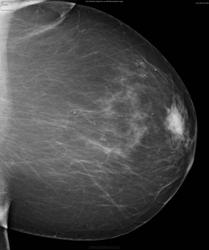

Маркировка на снимках есть.. Извините за глупый вопрос - никак не дойдет, какой же участок снимали прицельно? В косой проекции ассиметрия бросается в глаза (и то в правой железе) но в прямых не вижу участка который бы зацепил, а прицельный как я понимаю выполнен в прямой

Опухоль находится в субареолярной области слева. К счастью -пальпировалась.Мы выполнили стандартное исследование- результат(Вы видите) не убедительный. Потом пальпаторно выявили подозрительное место и выполнили прицельный снимок.Ориентиром была пальпация. Я представил этот случай к рассуждениям о проведении маммографии только в косых проекциях. В данном случае полноценного исследования(в 2-х стандартных проекциях) оказалось мало.